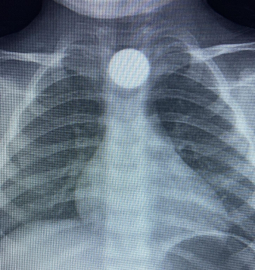

Yavuz YILMAZ/İNEGÖL (Bursa), (DHA)- BURSA’nın İnegöl ilçesinde evde bulup yuttuğu 50 kuruş madeni para yemek borusunda takılı kalan Bilal K. (3), hastanede tedaviye alındı.

Olay, kırsal Yeniceköy Mahallesi’nde meydana geldi. Bilal K., evde oynarken yerde bulduğu 50 kuruş madeni parayı ağzına alıp yuttu. Durumu fark eden ailesi, Bilal K.’yi özel araçla İnegöl Devlet Hastanesi’ne götürdü. Hastanede yapılan kontrollerde, madeni paranın Bilal K.’nin yemek borusunda takılı kaldığı belirlendi. Burada ilk müdahalesi yapılan Bilal K., daha sonra ambulansla Bursa Yüksek İhtisas Eğitim ve Araştırma Hastanesi’ne sevk edildi.

Bilal K.’nin tedavisinin sürdüğü öğrenilirken, olaya ilişkin soruşturma başlatıldı. (DHA)